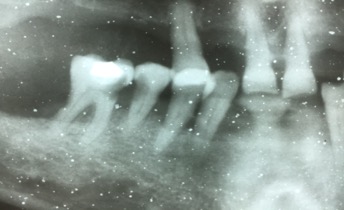

Un paciente varón de 43 años viene a consulta con un fuerte dolor en la zona inferior derecha. Tras una exploración radiográfica, vemos cómo el segundo molar inferior derecho presenta una caries de gran tamaño provocada por la posición de la muela del juicio inferior derecha.

La inclinación de esta muela del juicio impacta sobre el segundo molar, provocando al final esta desafortunada situación clínica que, en cierta medida, nos obliga a tomar la decisión de retirar las dos muelas, ya que los dolores que sufre el paciente son realmente fuertes.